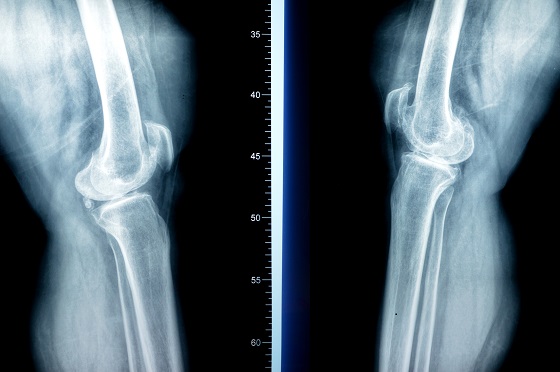

Osteofite la nivelul genunchilor

-

frecvente in gonartroza (artroza genunchiului);

pot aparea pe femur, tibie sau rotula;

simptome: durere la mers, care se accentueaza la coborarea scarilor, pocnituri sau trosnituri (crepitatii) in timpul miscarii, umflarea usoara a genunchiului, limitarea flexiei si extensiei.

radiografie: evidentiaza clar excrescentele osoase;